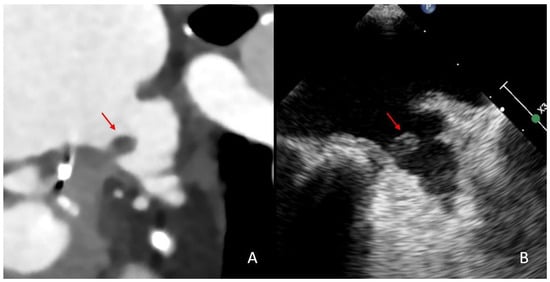

2.4. Imaging Analysis